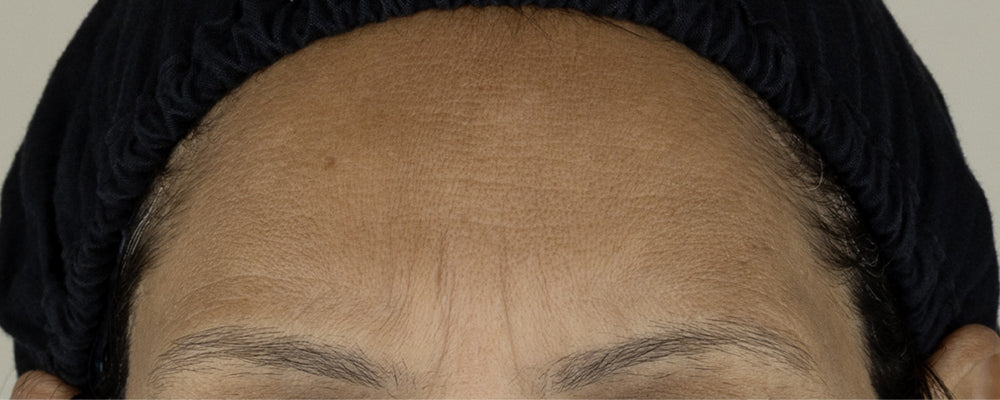

Clinically Proven Results

After 28 days

After 14 days

After 7 days

Before

After